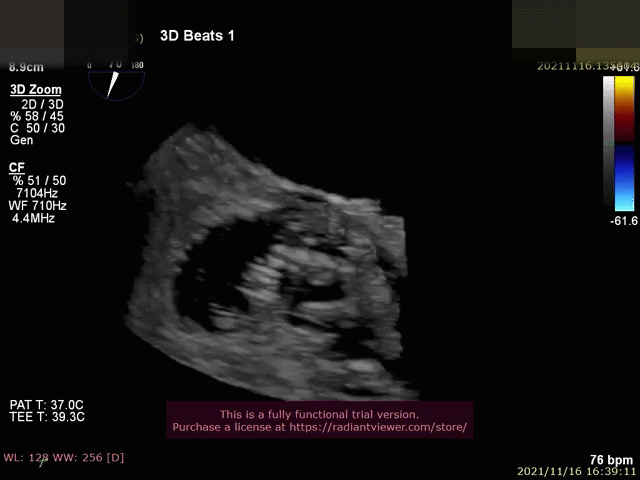

患者为一名77岁高龄的老年女性,罹患极重度三尖瓣反流,临床症状明确,合并高血压,房颤,右心功能不全等多种并发症,经多学科讨论判定为传统外科手术高危患者,经伦理委员会讨论批准,行经导管介入三尖瓣修复技术。术前经胸超声提示极重度三尖瓣反流(图1)。

图1:术前TEE、TEE提示极重度三尖瓣反流。